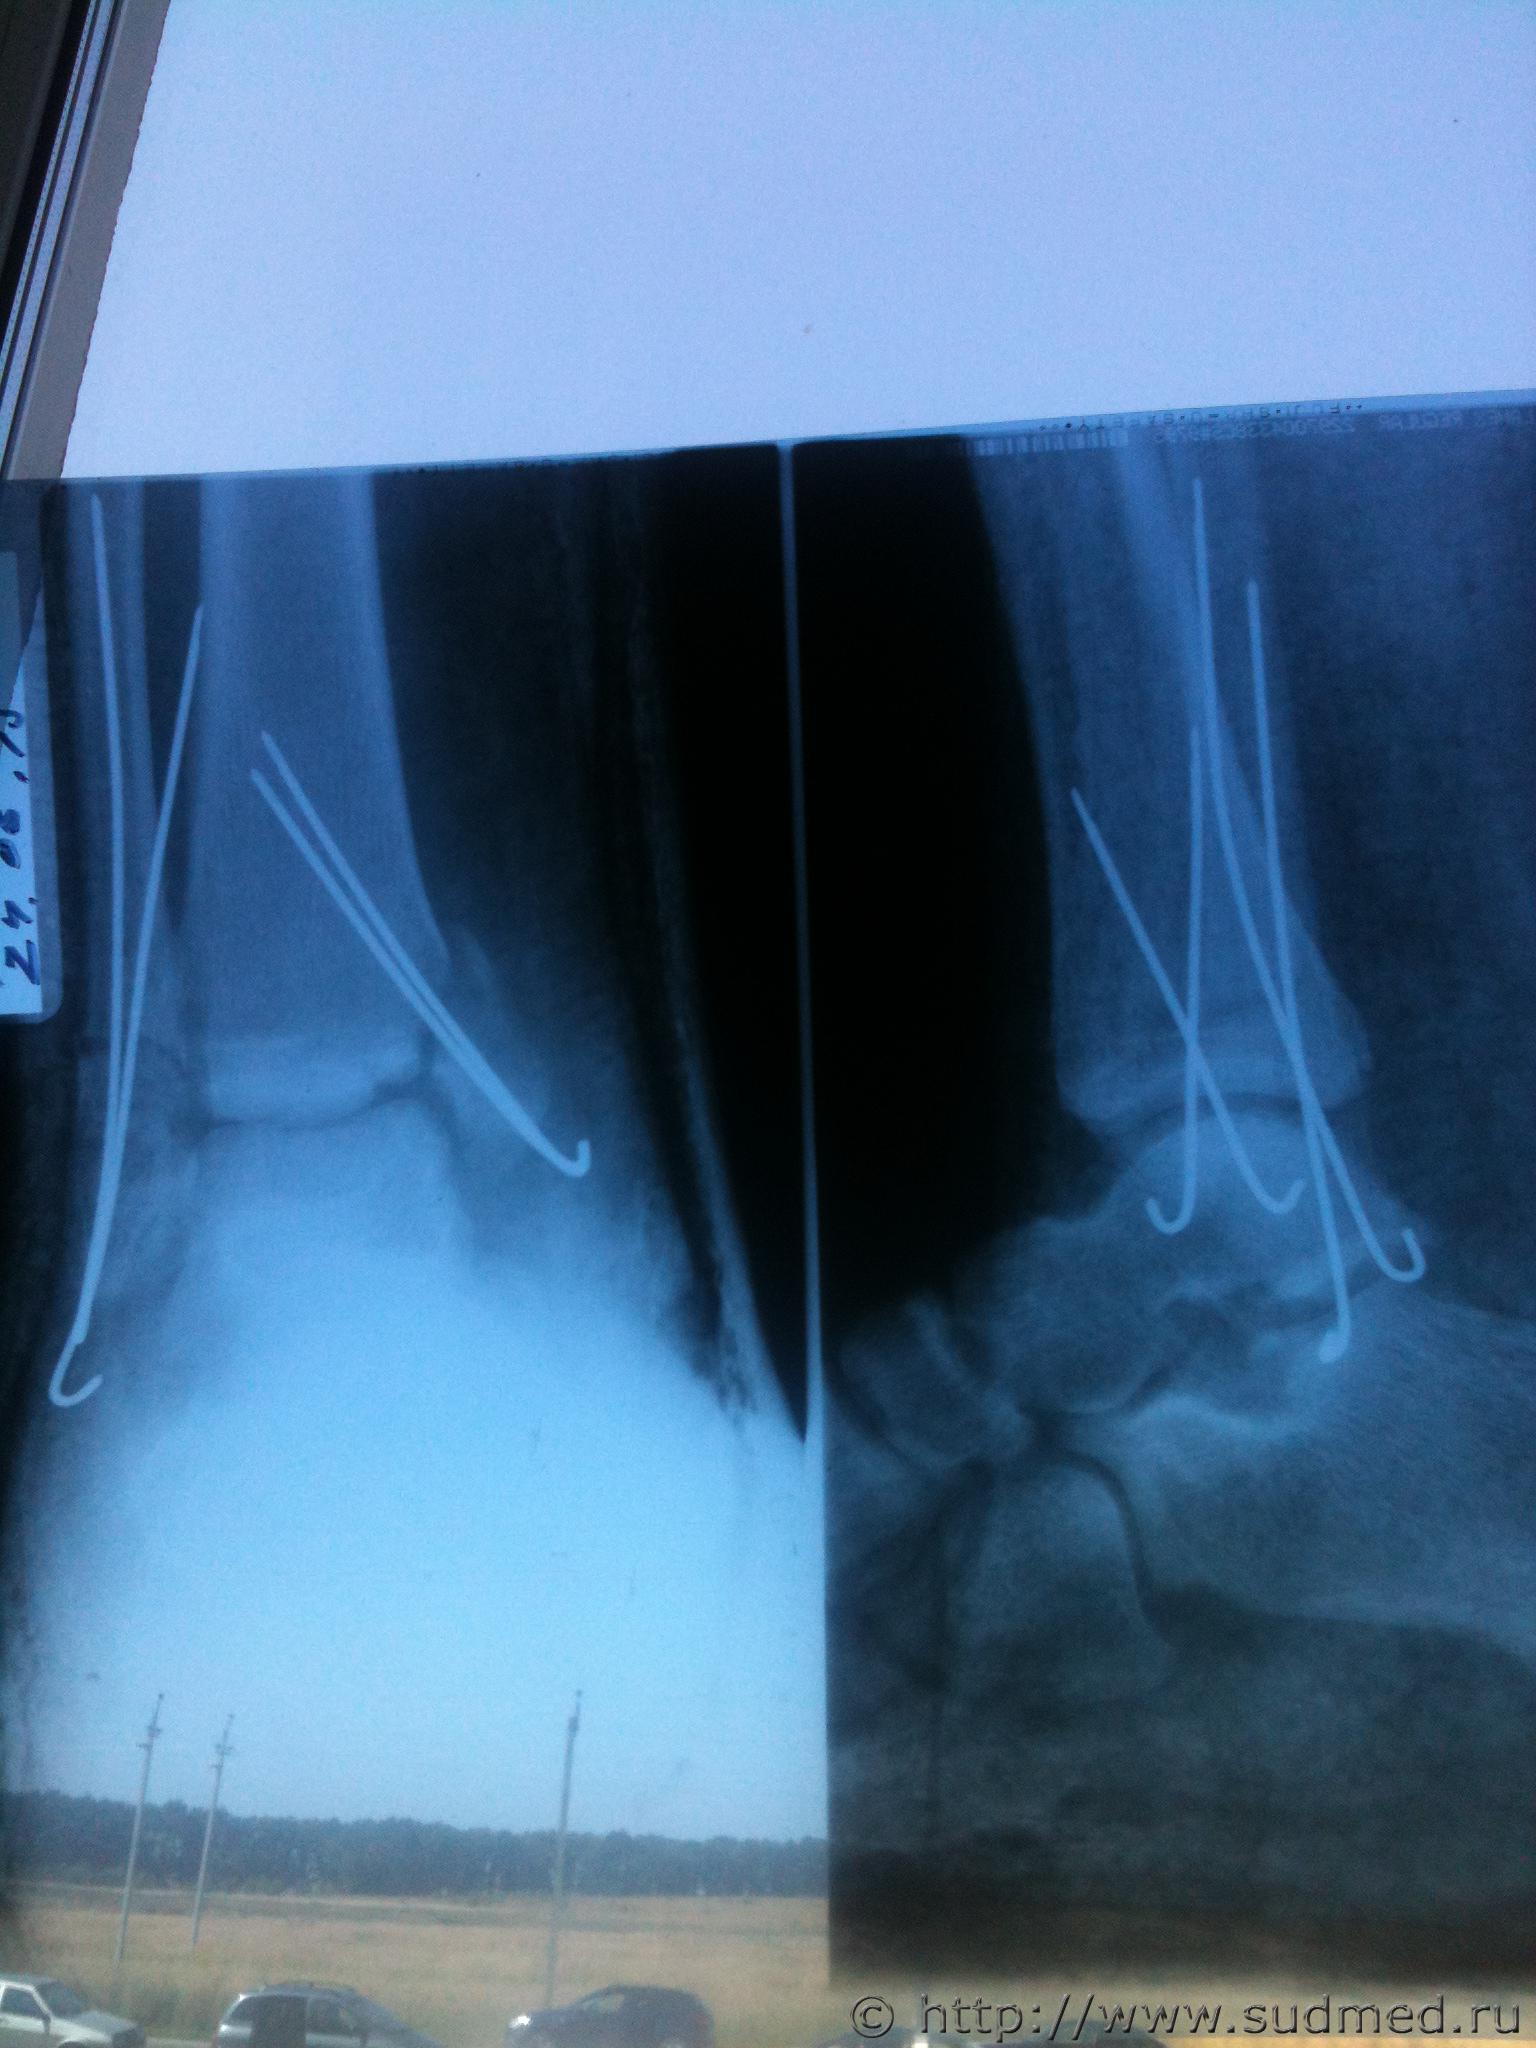

По возможности, выложите первичные рентгенограммы, с описанием их рентгенологом и протокол операции.

Судя по представленным рентгенограммам - переломы внутренней и наружной лодыжек. Если кроме этого ничего другого "серьезного" не обнаружено - вред здоровью средней тяжести.